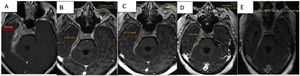

A biopsy was taken of the lesion in January, reporting: proliferative lesion which combines elongated fibrous elements, partially in a spindled or fascicular arrangement and swirled with collagenized bands together with an abundant and dense lymphocytic inflammatory component, dispersed and in accumulations, frequent plasma cells and some macrophages. No necrosis, mitosis or cytologically atypical cells were observed. We interpreted these findings as suggestive of an inflammatory myofibroblastic tumour. Other diseases such as meningioma or cholesteatomatous reaction were ruled out (Figs. 2A and B).

The biopsy was studied again and an immunohistochemical examination revealed abundant non-storiform fibrosis, between which glandular structures coated in pseudostratified ciliate epithelium without atypical features, which could correspond to trapped native epithelium, and predominantly lymphoplasmacytoid infiltrates.

Histiocytes were also recognised in other slices, as were foci of polymorphonuclear cells (mastoid areas), within the context of prominent endothelial congestive vessels. No granuloma formations or frank necrosis were observed. No increase of eosinophils or obliterating phlebitis was seen (no elastin staining was performed).

Special stainings were used (PAS and Ziehl-Neelsen), without detecting the presence of specific germs.

Immunohistochemistry: all of the controls showed correct reactivity. IgG4: 50–60 plasma cells IgG4+ per high power field. IgG4/IgG ratio: 15%–20% (Fig. 2C and D).

CD68: positive in histiocytes. CD1a: negative. S100: negative (staining in peri-epithelial dendritic cells).

One month after commencing treatment a follow-up NMR imaging scan showed a reduction in the involvement of vascular and nerve structures around the cavernous sinus, the optic chiasm, a reduction in the cerebral parenchymal oedema and reduction in meningeal thickness and enhancement in the base of the cranium.

Comparatively, a partial response to the treatment that commenced after the basal study was observed. This study had found a pachymeningeal thickness of 19.5mm; in the follow-up imaging tests this thickness has reduced to 10.5mm (53% of its initial size) one week after the corticoid pulse; to 8.7mm (44% of the initial value) with corticoids plus rituximab; and in the final test 3 months after the start of treatment, with maintenance corticoid therapy of 10mg/day prednisone and methotrexate it measured 7.8mm (40% of its initial size) (Fig. 3A–D).

In the final check-up a reduction in pachymeningeal thickening described in the previous studies was observed, at the level of the chiasma, the internal acoustic canal, the cavernous sinus and the temporal fossa. When slices were performed later after 30min. greater enhancement of the pachymeningeal tissue was observed in comparison with the fibrotic component (Fig. 3E).